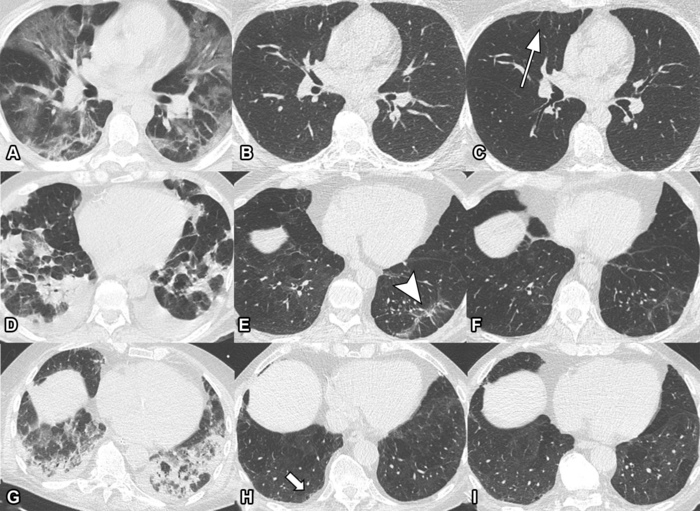

March 29, 2022 Some people recovering from COVID-19 pneumonia have CT evidence of damage to their lungs that persists a full year after the onset of symptoms, according to a new study published in t… [+3860 chars]